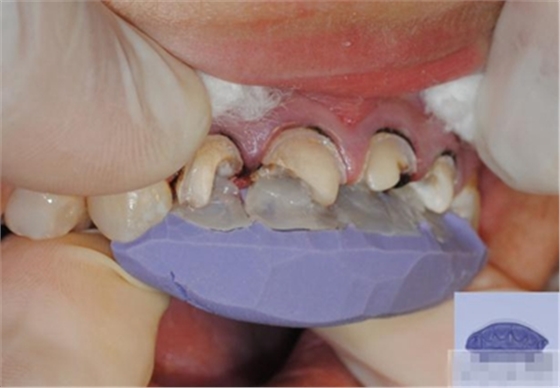

【檢查】12,11,21,22,均行玻璃離子充填,各牙不同程度部分充填物脫落,探(—),叩(—),冷刺激無反應(yīng),無松動(dòng),牙齦顏色粉紅,質(zhì)地堅(jiān)實(shí)而有彈性,點(diǎn)彩正常,牙結(jié)石(—);牙髓活力測試無反應(yīng)。

1.美容評(píng)估,取模體外制備舌側(cè)背板

樹脂修復(fù)【診斷蠟型制作】美學(xué)蠟型可以使患者對(duì)可以達(dá)到的修復(fù)效果有直觀的了解,而且,患者也可以依據(jù)自己的美學(xué)素養(yǎng)對(duì)修復(fù)效果提出修改的意見;

制作舌側(cè)背板